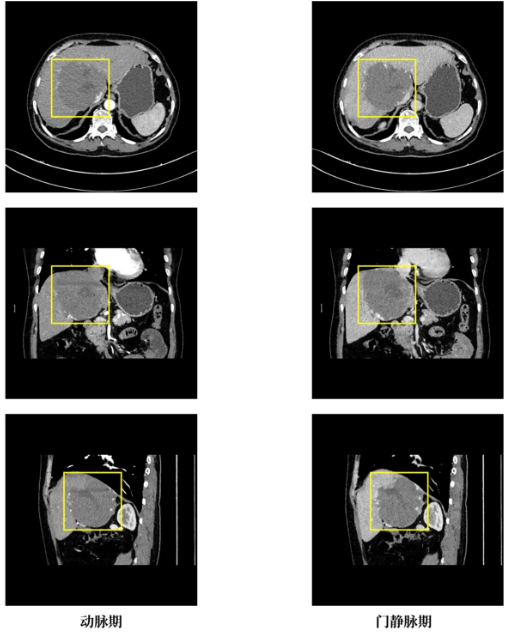

据介绍,来自毕节市的张女士经检查发现肝右叶-左内叶及尾状叶存在巨大海绵状血管瘤,此病变累及肝右叶-左内叶及尾状叶区域,毗邻肝脏重要血管,对周围胆管已形成压迫侵犯,解剖关系错综复杂,手术中稍有不慎便可能引发大出血、血管损伤等致命风险。因该手术因病变位置刁钻、解剖结构复杂,被业内视为肝脏外科微创领域的“硬骨头”。面对这一棘手情况,省医肝胆外科二部迅速组建多学科诊疗小组,反复研讨患者的影像学资料与身体指标,精准规划手术路径,最终敲定腹腔镜微创治疗方案。术后钱女士恢复顺利,各项生命体征平稳。